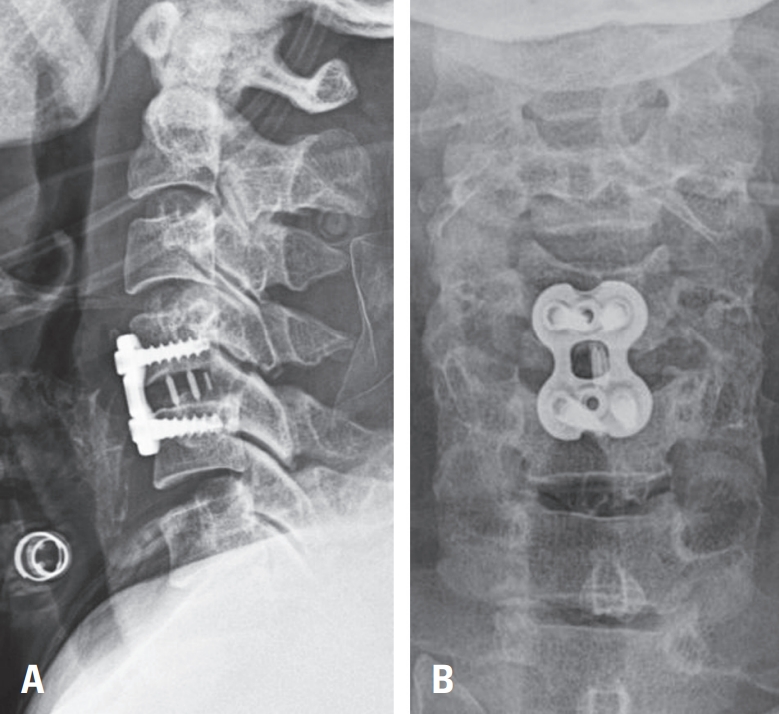

60-year-old woman presented following a motor vehicle collision with notable upper extremity weakness. On examination, motor strength was 2/5 in the left arm and 3/5 in the right arm. Cervical spine radiographs revealed dislocation at the C4–C5 level (

Fig. 1A). Computed tomography demonstrated locking of the left facet joint and subluxation of the right facet joint (

Fig. 1B). Magnetic resonance imaging showed spinal cord compression at C4–C5 with corresponding intramedullary signal change (

Fig. 1C).

To evaluate for vertebral artery injury secondary to facet dislocation, neck CT angiography was performed, confirming occlusion of the left vertebral artery at C4–C5 (

Fig. 1D). As there were no acute posterior circulation symptoms, the patient underwent urgent anterior cervical discectomy and fusion (ACDF) at C4–C5 to relieve cord compression (

Fig. 1.

(A) Lateral cervical spine radiograph demonstrating traumatic anterior translation at C4–C5. (B) Cervical spine CT showing left C4–C5 facet dislocation. (C) Cervical spine MRI revealing spinal cord signal change at the C4–C5 level. (D) Neck CT angiography demonstrating occlusion of the left vertebral artery at C4–C5 secondary to facet dislocation.

Fig. 2.

(A, B) Postoperative cervical spine radiographs (anteroposterior and lateral views) demonstrating anterior cervical discectomy and fusion (ACDF) at C4–C5.